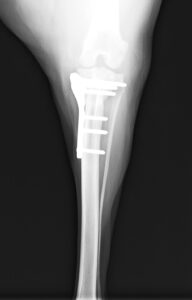

ジャンプした拍子に右後肢跛行とのことでかかりつけ医を受診後、セカンドオピニオンとして当院の整形外科に来院されました。若い雄猫に多く見られる「大腿骨頭すべり症」と診断。ご家族様と相談の上、骨頭切除を実施しました。経過は順調でしたが、その6ヶ月後に逆側も同様に骨折し、同治療を行いました。結果的に両側の骨頭切除が行われましたが、経過は良好です。